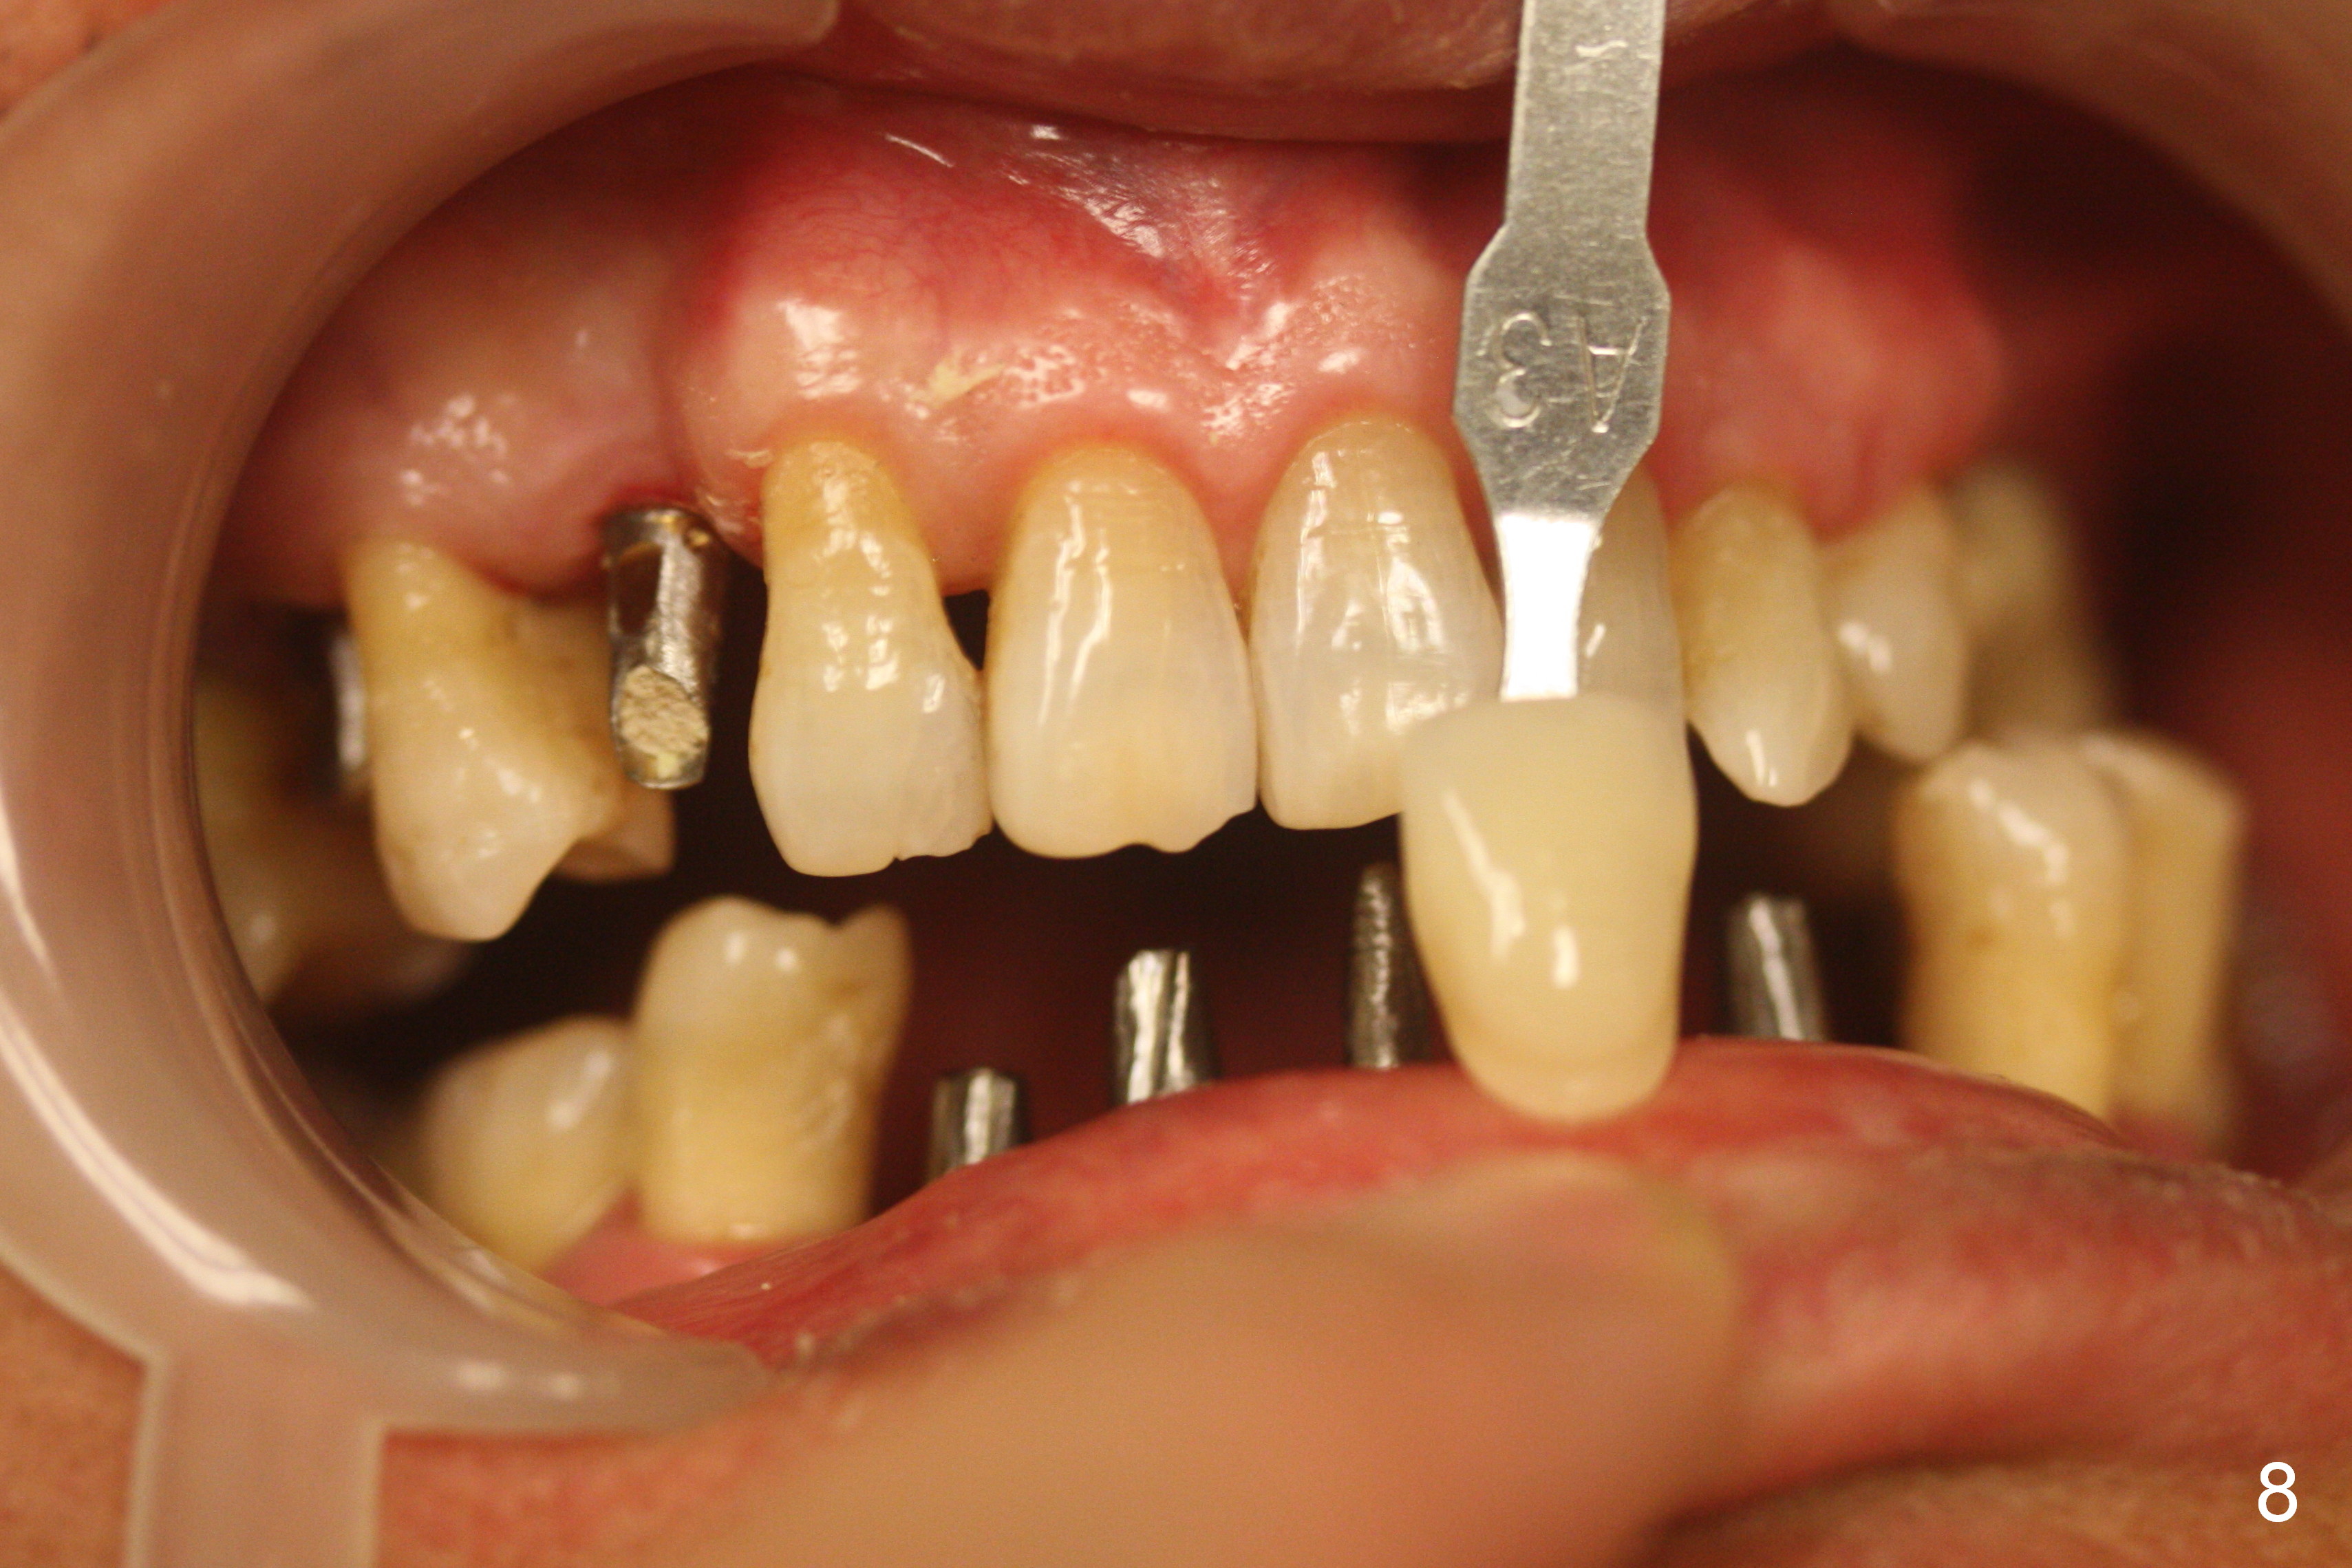

The patient returns for restoration 4.5 months postop (Fig.7-9).  There appears bone growth around the implants.  Impression is taken together with the implants at #4 and 6.

When the final crowns are seated, the shade is off.  It appears that C3 is appropriate (Fig.10,11).  Please make the crowns more transparent.